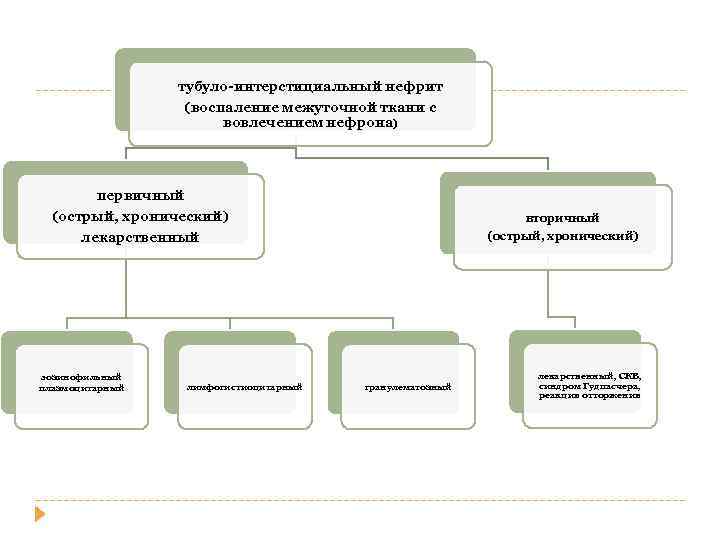

тубуло-интерстициальный нефрит (воспаление межуточной ткани с вовлечением нефрона) первичный (острый, хронический) лекарственный эозинофильный плазмоцитарный лимфогистиоцитарный вторичный (острый, хронический) гранулематозный лекарственный, СКВ, синдром Гудпасчера, реакция отторжения